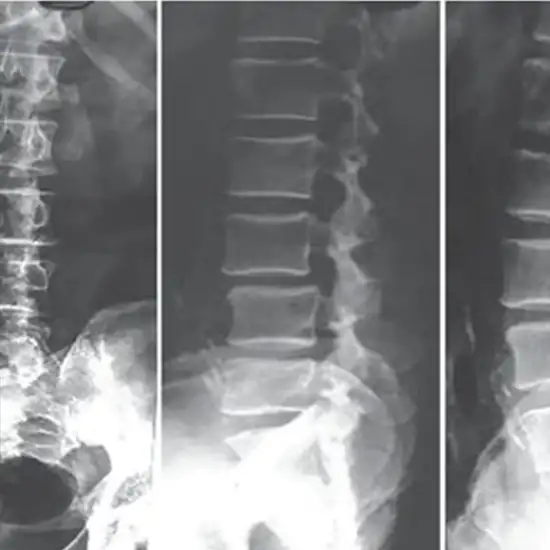

X-Ray Lumbar Spine (AP/Lateral/Oblique)

The X-Ray Lumber Spine examination allows your physician to examine the skeletal structure of your lower back.

Having an X-ray of your lower back may be recommended by your doctor to see if there are any injuries, abnormalities, or diseases in your bones. The X-ray is not a reliable diagnostic tool for any condition other than osteoarthritis and fractured bones since it cannot detect abnormalities in nerves, muscles, or discs.